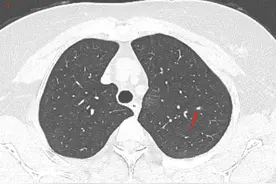

对于刚发现的直径比较小的肺磨玻璃结节,观察一段时间,看看它的变化,再决定是不是手术,是绝对安全的。有一位家住天津55岁的女士,偶然的原因拍胸部CT,发现了肺部有两个磨玻璃结节,她带着片子过来找我看,我看到这两个结节都比较靠近外周,大的那个有6毫米,看起来恶性的可能性比较大,但直径比较小,可以再观察一下。

简单来说,他们也和小孩子一样,从小婴儿开始慢慢成长,努力锻炼生存技巧,并最终获得侵袭转移的能力。而1cm以下的小肺癌尚处于襁褓期,侵袭性通常很弱,不会发生淋巴结转移,如果能在这个阶段进行干预,效果自然也很好。